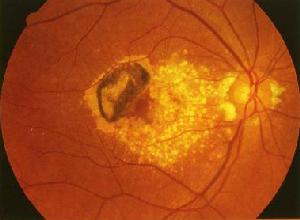

角膜老年環移植角膜潰瘍因致病菌種不同,其形態不一致。早期潰瘍為淺在性,表層有點狀結節樣浸潤,呈灰白色或乳白色混濁;形狀不規則,表面粗糙不平,有乾性感,與健康角膜界限清楚。壞死組織無粘性,易取掉。深在型潰瘍,除自覺症狀較重外,表現形似“匐行性角膜潰瘍”,潰瘍面平而粗糙,呈“舌苔”或“牙膏”狀,高起於角膜表面。基質有菌絲繁殖,浸潤較為緻密。因菌絲伸入潰瘍四周而形成偽足,或在潰瘍外圍呈現出所謂“衛星”病灶。有時在潰瘍邊界處可出現淺溝。在潰瘍向深部發展時,壞死組織脫落,角膜穿孔,或出現“露水”現象,可推測前房已消失。有時在壞死的角膜中,夾雜有虹膜組織,表示潰瘍已穿孔。